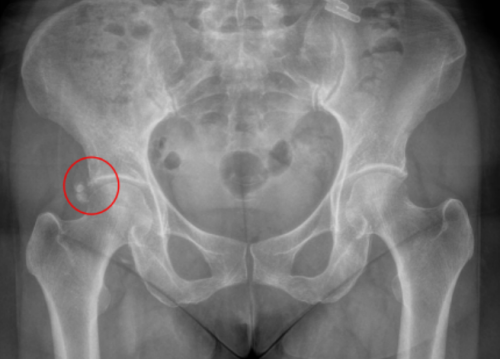

红圈内的“小石子”就是患者右髋关节处钙化灶

“钙化性肌腱炎是钙盐沉着于肌腱(最常见于肩关节的肩袖肌腱)中,导致关节疼痛和功能障碍的一种疾病。”丑克主任介绍,髋部钙化性肌腱炎发病罕见,通常是无诱因的突发关节剧痛,臀部或髋部疼痛,且症状在运动后加重。这些疼痛可能会向下放射至大腿前侧甚至小腿,也可能伴有运动障碍、晨僵等症状,严重时甚至会影响到日常活动和工作。

钙化性肌腱炎的确诊需要借助多种检查手段。X光片上可以看到肌腱中特有的钙化阴影;超声检查则能更直观地观察到钙化灶的形态和分布;磁共振成像能够清晰显示病变范围及其对周围组织的影响。